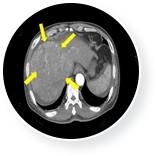

이때 3개월 간 매주 1회 일정으로 총 12회의 면역세포 치료를 실시하였고, 간암의 종양표 지자인 AFP가 치료 전 19,175(ng/ml)에서 치료 후 170(ng/ml)로 떨어졌습니다.

또한 CT검사 결과 간암의 축소 및 복수 소실이 확인되었습니다.

• 간암 치료 후  이미지

간암 치료 후